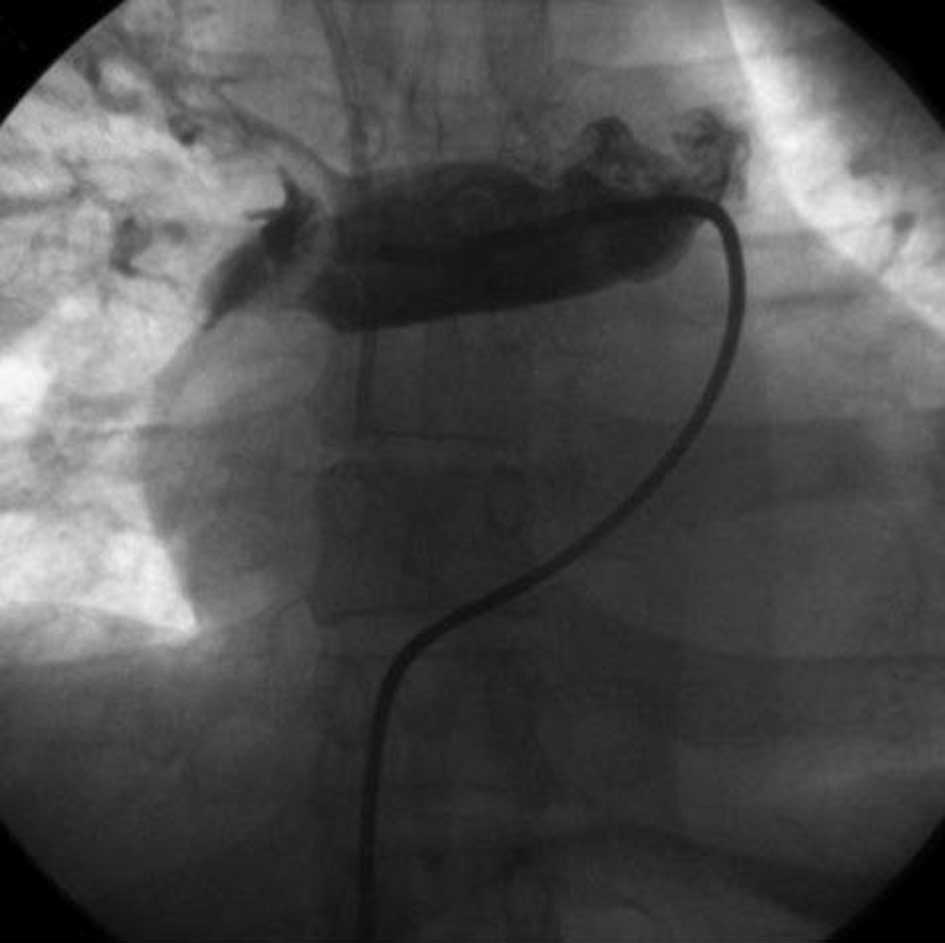

Following the above therapies, digital subtraction angiography (DSA) of the deep veins of the lower limbs and the inferior vena cava demonstrated unobstructed blood flow, with no apparent thrombosis. A 4–5F double J tube was inserted through the right femoral vein to the main pulmonary artery for DSA of the pulmonary artery, to confirm the filling defect in the right main pulmonary artery (Fig. 3). An exchange guide wire was then inserted to coordinate with the tube for twists and drags to disintegrate the embolus. Following disintegration of the embolus, 500,000 units urokinase were injected into the tube for thrombolysis over 30 min. Subsequent DSA of the pulmonary artery indicated an improvement in the filling defect compared with before treatment (Fig. 4). The patient’s condition was significantly alleviated and the anoxia was reduced. A blood gas assay performed 2 h after surgery indicated a pH of 7.51, 72 mmHg PaO2, 29 mmHg PaCO2 and 23.1 mmol/l HCO3− (under the condition of a low flow rate of oxygen inhalation).

Figure 3

Digital subtraction angiography of pulmonary artery confirming the filling defect in the right pulmonary artery.